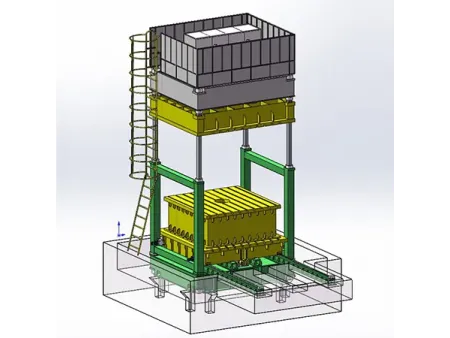

El modelo SHO-CMX01 es un sistema de rayos X fijado al techo pensado para quienes buscan precisión, rapidez y calidad en sus exámenes de imagen. Ideal para estudios de tórax, columna, abdomen y extremidades, se adapta perfectamente a centros médicos, departamentos de radiología, unidades de ortopedia y diagnóstico, entre otros. Este dispositivo médico no solo cubre radiografías convencionales, sino que también está preparado para procedimientos más exigentes como uniones de imágenes, visualización detallada de fracturas o estudios integrales en reconocimientos médicos. Es una solución integral que responde a las demandas clínicas más exigentes.Está equipado con un generador de 65.5 kW, un tubo de rayos X Canon de muy buen rendimiento, y dos detectores de panel plano (uno con cable y otro inalámbrico) que garantizan imágenes nítidas. Además, su colimador motorizado le permite ajustar el campo de exposición de forma rápida y precisa, optimizando cada procedimiento.

El sistema radiográfico incluye una pantalla táctil de 10.4 pulgadas y una estación de trabajo completa con monitor, joystick, software de última generación de imagen y controles ergonómicos, lo que simplifica la operación y mejora el flujo de trabajo. Con este equipo, podrá enfocarse en lo más importante: ofrecer diagnósticos certeros y una atención médica de calidad.